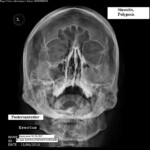

Ἡ ἁπλὴ ἀκτινογραφία παραρινίων ἀποτελεῖ τὸν συχνώτερα χρησιμοποιούμενο ἀκτινολογικὸ ἔλεγχο (εἰκ. 3). Στὴν περίπτωση αὐτὴ (προβολὴ κατὰ Waters σὲ ὄρθία στάση μὲ ἀνοιχτὸ στόμα) τὸ πάχος τοῦ φυσιολογικοῦ βλενογόνου τῶν ἰγμορείων δὲν πρέπει νὰ ὑπερβαίνει τα 3mm. Ἐὰν τὸ πάχος εἶναι 3-5 mm ἔχουμε ἐλαφρὰ φλεγμονή, 5-10 mm ἔχουμε μέσης βαρύτητος φλεγμονή, καὶ ἐὰν>10mm τότε ἡ φλεγμονὴ χαρακτηρίζεται ὡς βαρειά. Ἡ ἐμφάνιση ὑδραερικοῦ ἐπιπέδου παραπέμπει σὲ ὀξεῖα φλεγμονή. Ὡστόσο ἡ ἁπλὴ ἀκτινογραφία δὲν εἶναι πάντα καὶ ἡ πιὸ ἐπαρκὴς καὶ ἀξιόπιστη μέθοδος καὶ σὲ περιπτώσεις δυσδιάγνωστες ὀφείλουμε νὰ καταφύγουμε στὴν βοήθεια τῆς ἀξονικῆς τομογραφίας (εἰκ.4), ὅπου δι’ αὐτῆς ἀποκτοῦμε πλήρη ἔλεγχο τῶν δομῶν τοῦ μέσου ρινικοῦ πόρου καὶ τῶν στομίων τῶν κόλπων, εἰδικὰ στὶς στεφανιαίες τομές. Τὸ μειονέκτημα τῆς μεθόδου αὐτῆς εἶναι πάντα ἡ ὑψηλὴ δόση ἀκτινοβολίας.